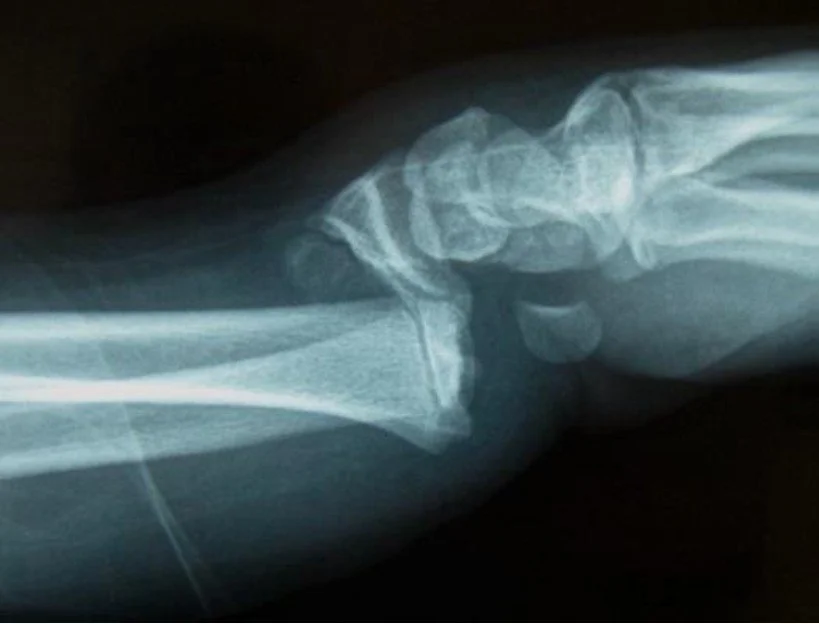

Arthritis Children Congenital Trigger Thumb Childrens Hand Fractures Childrens Wrist Fractures Ganglions Finger Tip Injuries Seymour Fracture